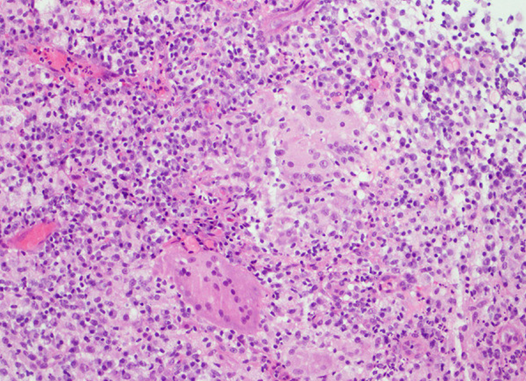

Ιστολογική εικόνα μη τυροποιητικών κοκκιωμάτων (Ευγενική παραχώρηση Dr. V. Penopoulos)